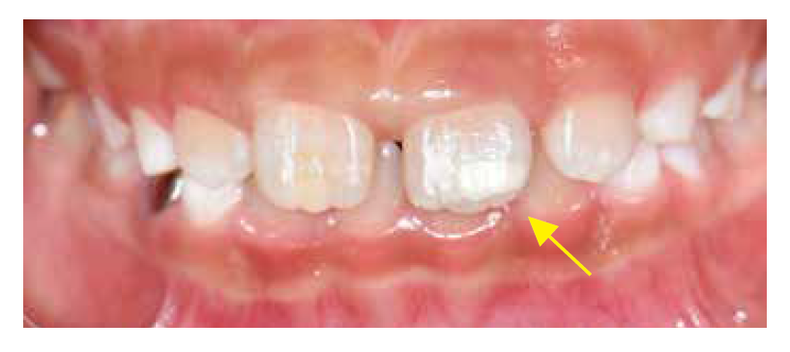

아이의 어금니와 앞니에 얼룩이 보인다면? 어금니-앞니 저광화(MIH)

전신적 원인으로 인해 하나 이상의 제1대구치(큰어금니)와 절치(앞니)에 발생하는 법랑질 저성숙을 의미합니다. 명칭은 다소 낯설지만, 소아치과 진료실에서는 생각보다 흔히 접하는 질환입니다. 이환 범위와 중증도에 따라 다르지만, 심한 경우 과민증, 통증, 치아우식 진행, 파절 등으로 이어져 아이의 삶의 질에 악영향을 줄 수 있습니다.

일반인뿐만 아니라 MIH 임상 경험이 많지 않은 의료진조차 MIH를 초기 치아우식이나 다른 질환과 혼동하기 쉽습니다.

1) 초기 우식(충치): 주로 구강 위생 불량으로 인해 잇몸과 치아 경계 부위에 생기는 탈회 현상입니다. 반면, MIH는 치태가 잘 끼지 않는 치아의 씹는 면(교두)이나 평활면 등에서도 발생할 수 있습니다.

2) 치아 불소증: 불소 과다 섭취로 발생하며, 경계가 불분명한 백색 선이나 구름 모양을 띠는 것이 일반적입니다. 불소증 치아는 오히려 충치에 강한 저항성을 보입니다.

3) 법랑질 형성부전(Amelogenesis imperfecta, AI): 유전적 원인으로 모든 치아에 전반적으로 형성 부전이 나타나며 가족력이 뚜렷합니다. 반면 MIH는 특정 치아(제1대구치와 앞니)에 국한되어 나타납니다.

4. 증상 및 문제점

MIH에 이환된 치아의 대표적인 증상은 과민증(Hypersensitivity)입니다. 다공성인 법랑질을 통해 외부 자극이 신경으로 빠르게 전달되어, 일상적인 식사나 칫솔질을 할 때도 통증을 느낄 수 있습니다. 이 경우 아이들은 통증 때문에 양치질을 기피하고 치과진료 자체를 두려워하게 됩니다.

이는 결국 플라크 침착과 충치의 급속한 진행으로 이어져, 광범위한 치관 파괴를 초래하기도 합니다. 치아 우식 병소가 발생하지 않더라도 MIH치아는 정상적인 저작력에도 치아의 일부가 깨지거나 마모되어 떨어질 수 있습니다. 치아 표면이 무너지는 경우에는 우식이 더욱 빠르게 진행될 수 있습니다.